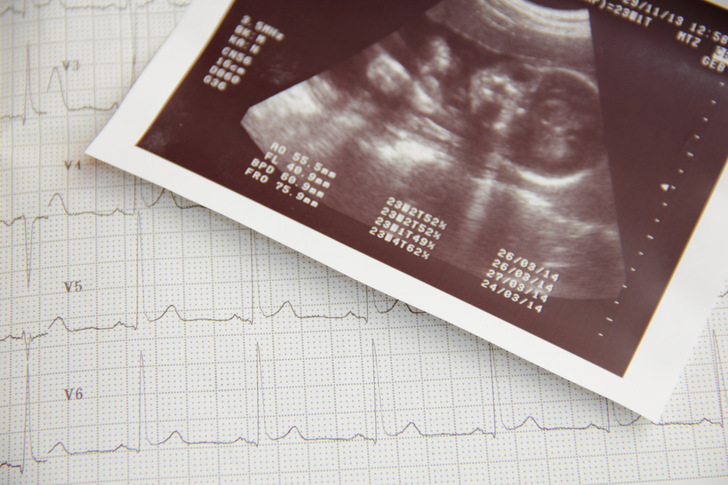

Deutschland zählt im weltweiten Vergleich zu den Ländern mit der niedrigsten Säuglings- und Müttersterblichkeit. Trotzdem bringt eine Schwangerschaft eine Reihe von Risiken mit sich. Eine Möglichkeit zur Überwachung des ungeborenen Kindes bietet das Kardiotokogramm (CTG), um die Herzfrequenz des Kindes und die Wehentätigkeit zu messen. Auch eine Dopplersonographie ist ein gängiges Instrument in der Schwangerschaftsvorsorge, welches als Ultraschalluntersuchung die Blutflussgeschwindigkeit misst. Ziel dieser Behandlungen ist die rechtzeitige Erkennung fetaler Gefahrenzustände, um intervenieren zu können, bevor eine Schädigung der Feten eintritt.

Nach einer ausführlichen Darstellung der wissenschaftlichen Daten zu Klassifizierungen von Low-risk-Schwangerschaften werden die Methoden und Vorgehensweisen zur Anwendung der genannten Ultraschallverfahren dargelegt. Während diese Verfahren früher zu den Standarduntersuchungen vor einer Geburt gehörten, werden Sie mittlerweile nur noch im Falle einer Schwangerschaft, für die ein erhöhtes Risiko festgestellt wurde, durchgeführt. Auch die AutorInnen dieser Leitlinie kommen auf Grundlage zahlreicher Studien zu dem Schluss, dass im Falle einer Low-risk-Schwangerschaft weder eine Dopplersonographie noch ein CTG notwendig ist. Die Analyse der Datenlage zeigte keine Evidenz, dass diese Verfahren zur Überwachung von Feten zu einer Reduktion der Morbidität und Mortalität führen. Für dieses Vorgehen wurde damit erstmalig eine ausführliche Grundlage geschaffen, welche die ausschlaggebende Evidenz zu diesem Thema bündelt und eine fundierte Handlungsempfehlung ableitet.